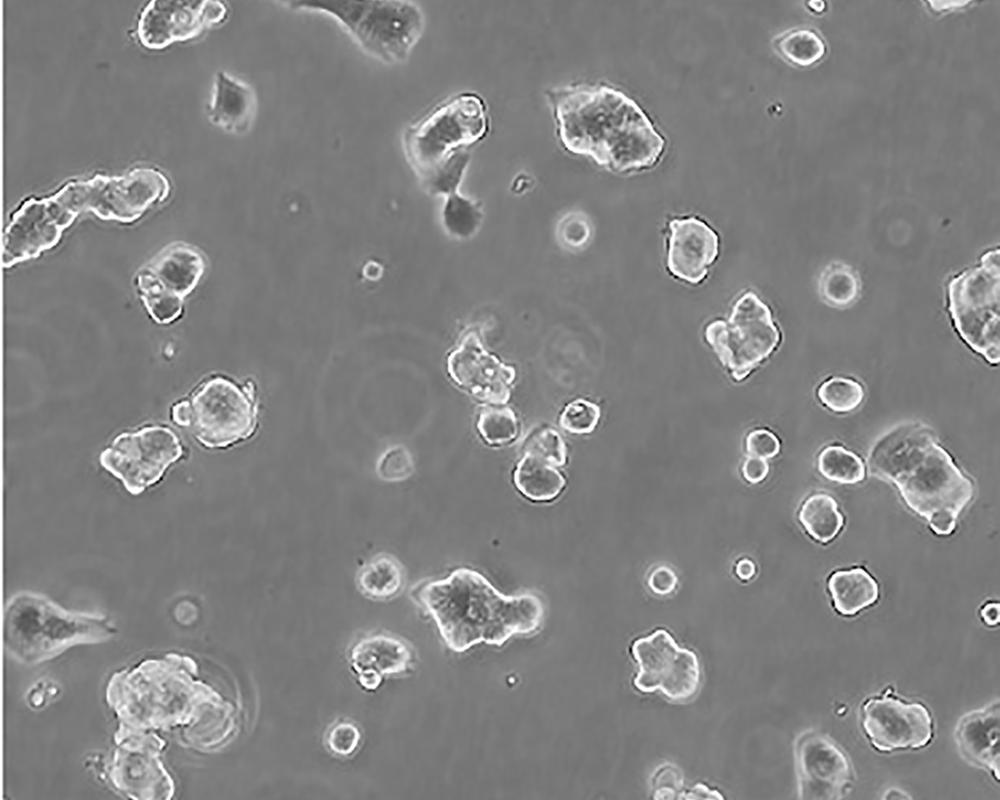

生長特性 adherent

形態特征 epithelial

細胞描述 該細胞產生高水平的黏液素MUC-1 mRNA,低水平的MUC-2 mRNA,但不表達MUC-3基因;表達雌激素受體。